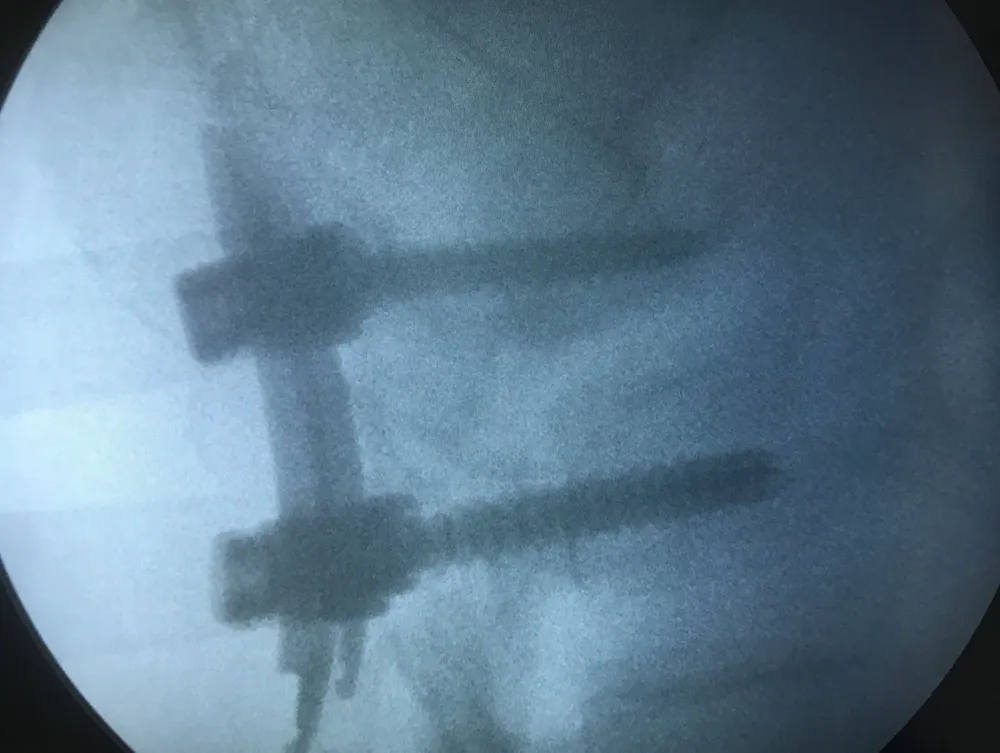

Ảnh chụp máy C-arm cho thấy vít được đưa vào cơ thể bà Đ. Ảnh: LÊ PHỤNG

Bác sĩ khoa Ngoại thần kinh và Gây mê hồi sức tiến hành phẫu thuật. Các BS dùng máy C-arm để xác định vị trí chân cung L5, S1 hai bên. Tiếp đến, bà Đ được rạch các đường mổ nhỏ khoảng 1 cm tại những vị trí cần bắt vít và rạch da cách đường giữa lưng 3 cm về hai bên. Sau đó, bác sĩ bắt vít và dùng dụng cụ phẫu thuật đặc biệt đưa vào bên trong cố định cột sống. Ca phẫu thuật kết thúc trong vòng hai tiếng. Sau phẫu thuật một ngày, bà Đ. có thể đi đứng, vết mổ không còn đau và tình trạng đau lưng giảm hẳn.